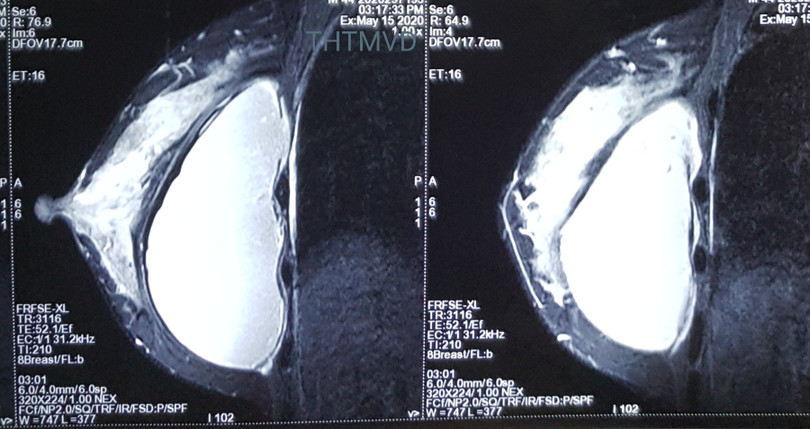

PGS.TS. Nguyễn Hồng Hà - Trưởng khoa Phẫu thuật Tạo hình Thẩm mỹ - cho biết: Người bệnh đến viện trong tình trạng lo lắng, bất an, thăm khám kỹ nhận thấy bề mặt túi ngực nhấp nhô không đều kết hợp. Hỏi kỹ tiền sử cho thấy chị V. đã được đặt túi nhám to giọt nước. Nhận thấy có đề bất thường, các bác sĩ đã chỉ định chụp cộng hưởng từ bằng máy 3.0 Tesla. Đây phương tiện chuyên dụng hiện đại nhất trong chẩn đoán các bệnh lý tuyến vú hiện nay. Kết quả chụp MRI cho thấy hình ảnh túi ngực đã vỡ từ trước mà chị V. không biết. Chính vì thế, chị V. đã được chỉ phẫu thuật ngay lập tức.

| Hình ảnh túi ngực của bệnh nhân (Ảnh: Bệnh viện Hữu nghị Việt Đức) |